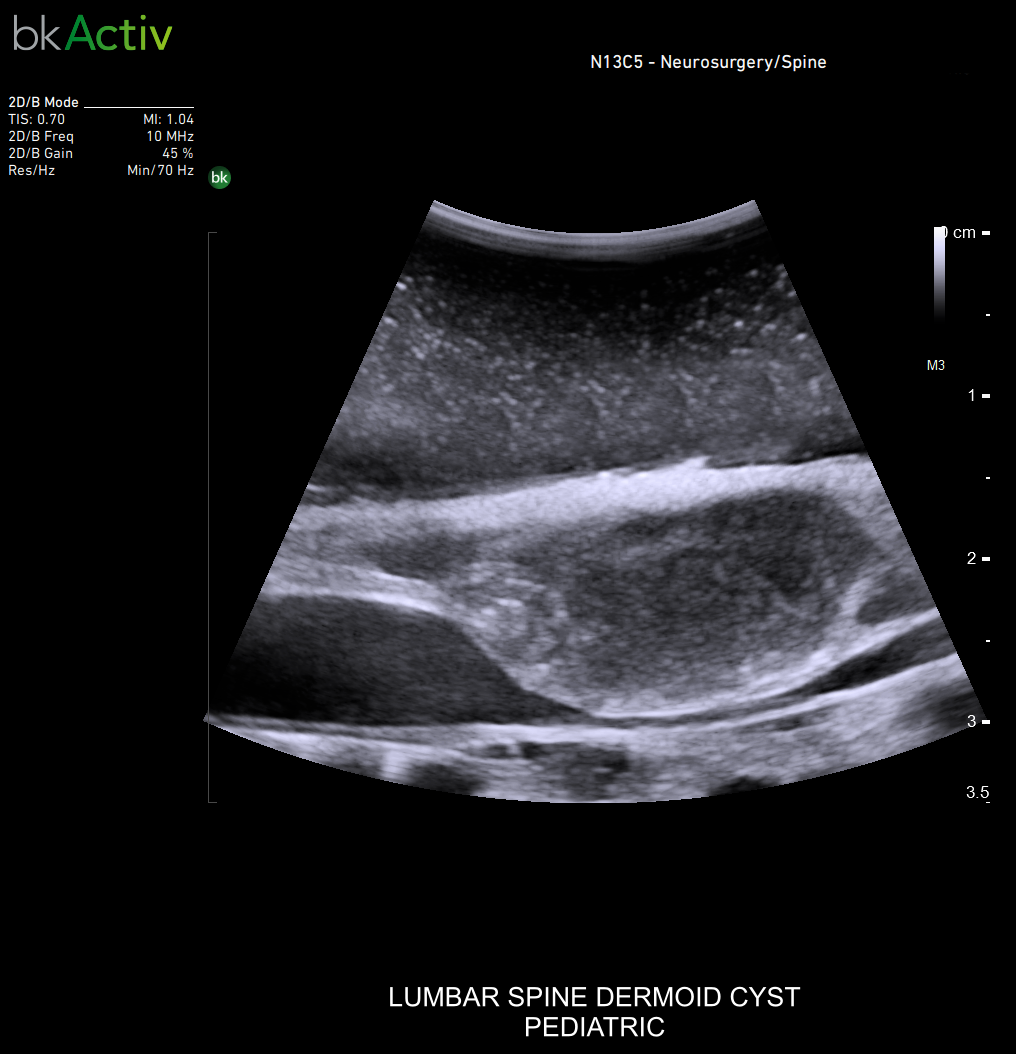

Neurosurgery and Spine

Improved algorithms that automatically allow uniform image resolution, greater details around lesion borders and at larger depths, and enhanced penetration, spatial resolution, and near field image quality.

N11C5s Transducer (9063) has been cleared for adults and children (>2 – 12 years).